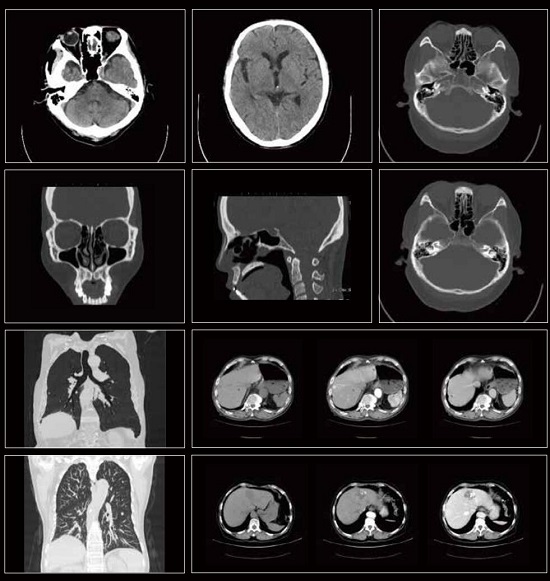

Features: - A high-end 32-slice CT with Optimal Resolution - Professional & Accurate, Delicate & Comprehensive - Low Dose Technology - Super-fast workflow - One-key intelligent Scanning - High-Speed Reconstruction System